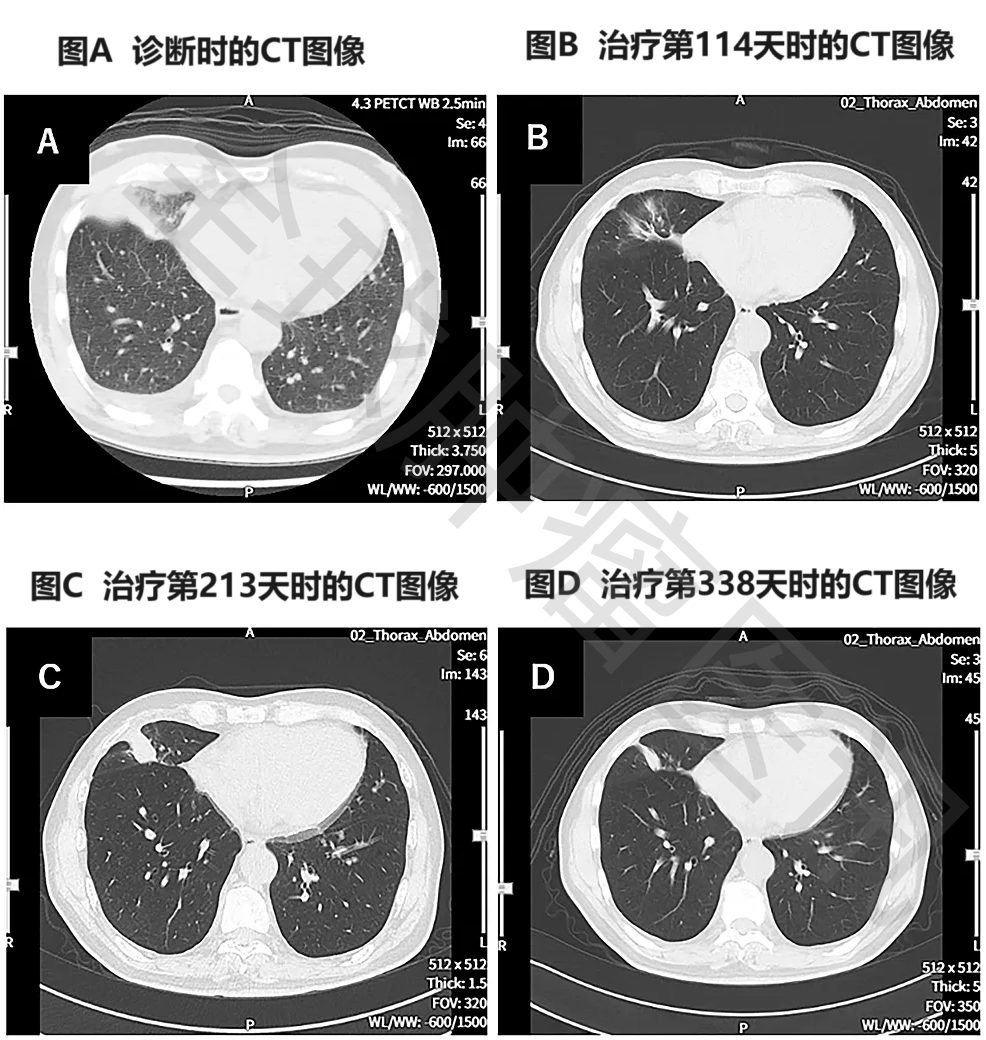

《Cureus》报道了一个“伴全身转移的终末期肺癌患者,经WT1-DC联合二线化疗后,获得长期显著缓解”的案例。本例患者为一名69岁的男性,确诊为右肺中叶IV期鳞状细胞癌,且伴双侧肾上腺转移、多发性骨转移、肝转移,此时已无法耐受手术及放疗等传统治法。入组接受WT1-DC+联合化疗(卡铂AUC6+紫杉醇)治疗后,结果显示如下:

2、癌胚抗原(CEA):癌胚抗原从诊断时的66.4,下降至3.0(治疗第121天)。

3、胸部CT显示:该患者在治疗第114天,复查胸部CT显示,肿瘤明显缩小(详见图2)。

图2  治疗前后胸部CT图像对比

注:

①图A示:原发性右下肺癌,同时伴左右胸腔积液。

②图B示:原发病灶几乎消失。

③图C示:原发病灶存在一定程度的复发。

④图D示:原发性及复发性病灶均缩小。